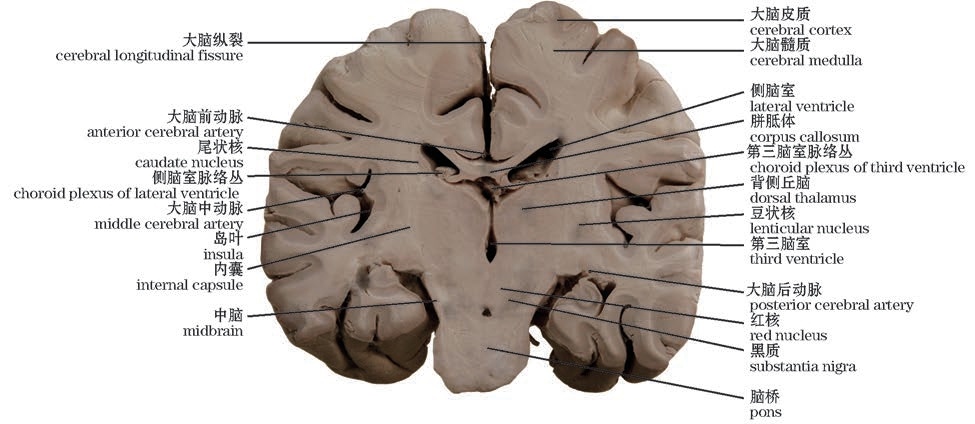

图10-12 脑冠状切面(经内囊)

The coronary section of the brain(Through the internal capsule)